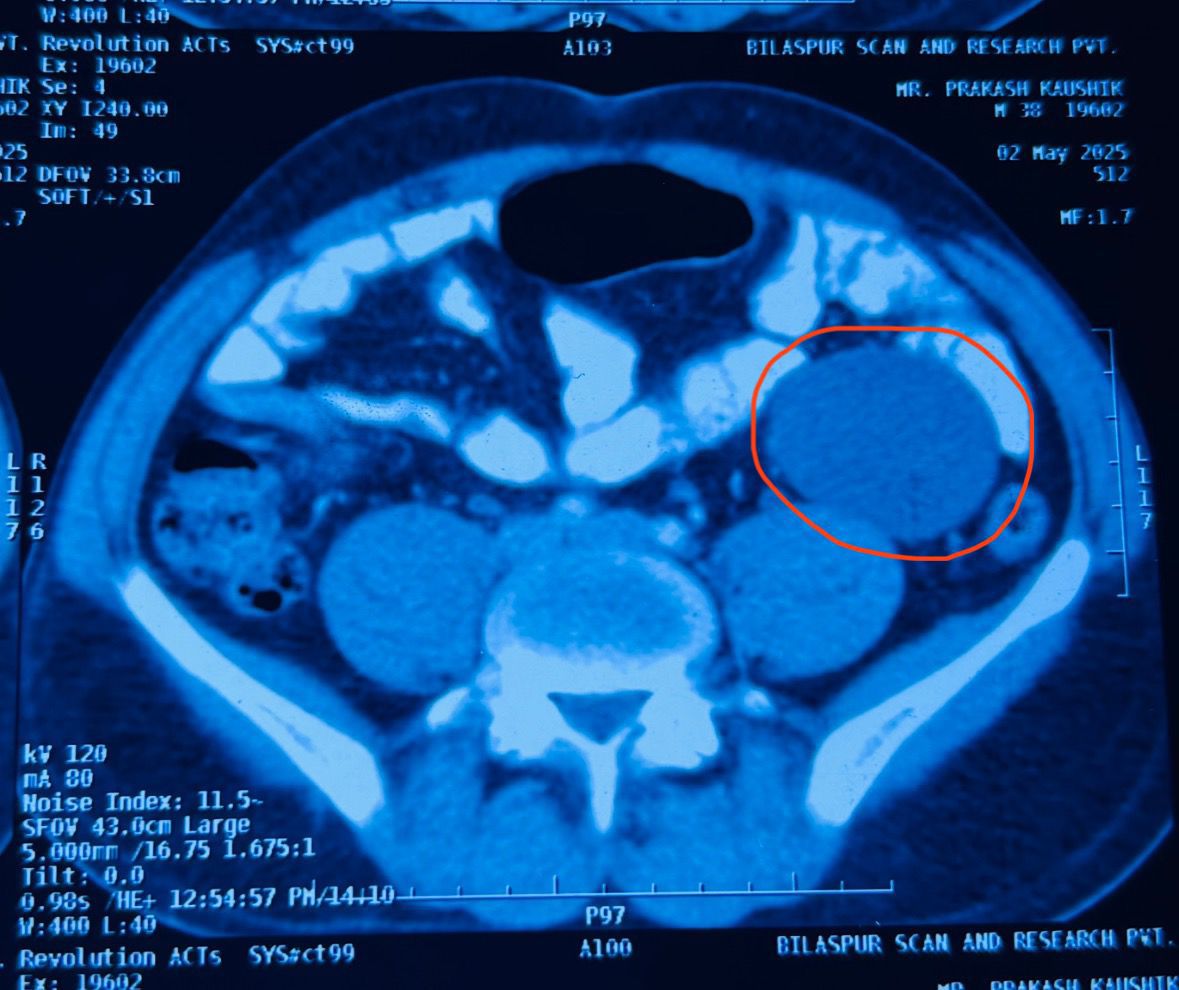

आर्थिक रूप से सशक्त न होने के कारण मरीज ने सिम्स की शरण ली और सर्जरी विभाग की ओपीडी में डॉ. रघुराज सिंह एवं डॉ. बी. डी. तिवारी को परामर्श हेतु दिखाया। आवश्यक परीक्षणों के बाद पता चला कि मरीज के पेट में लगभग 6×5 सेमी का मिसेंट्रिक सिस्ट मौजूद है, जो दर्द का मुख्य कारण था।

डॉक्टरों की विशेषज्ञ टीम द्वारा बिना बड़े चीरे के दूरबीन तकनीक से यह ऑपरेशन 10 मिलिमीटर और दो 5 मिलीमीटर छिद्र( चिरें) पेट में कर ऑपरेशन सफलतापूर्वक किया गया। यह प्रक्रिया सिम्स में पूर्णतः आयुष्मान कार्ड से नि:शुल्क की गई, जिससे मरीज और परिजनों ने गहरी संतुष्टि व्यक्त की।

सर्जरी टीम का नेतृत्व कर रहे डॉ. रघुराज सिंह ने बताया कि मिसेंट्रिक सिस्ट दुर्लभ मामलों में देखने को मिलता है और समय रहते ऑपरेशन आवश्यक होता है। सिम्स में ऐसी आधुनिक सर्जरी की सुविधाएं अब आमजन के लिए सुलभ हैं।